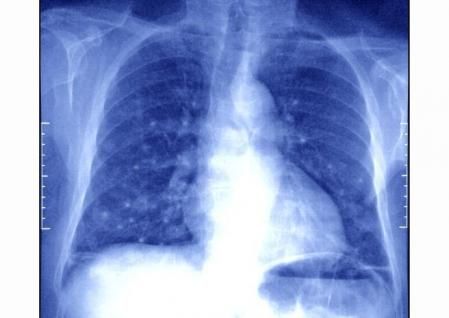

Nunca es tarde para dejar de fumar. Abandonar el consumo de tabaco a cualquier edad resulta beneficioso para la salud, puesto que no solo disminuye la acumulación de daños en el ADN, sino que, además, según un estudio del Wellcome Sanger Institute y del University College London (UCL), despierta a un grupo de células, hasta ahora desconocidas, que parecen ejercer un efecto protector contra e l cáncer .

Estas células, que no han sido dañadas por la exposición al tabaco, podrían encargarse de regenerar de forma parcial los pulmones, lo que podría ayudar a explicar por qué abandonar este hábito reduce el riesgo de desarrollar un tumor pulmonar

Ese descubrimiento, teniendo en cuenta que el de pulmón es la primera causa de muerte por cáncer en el mundo y que la Organización Mundial de la Salud (OMS) estima que 1,8 millones de personas mueren al año por esta enfermedad, arroja luz sobre la biología de este tipo de tumores y abre la puerta a que, en un futuro, se pudieran desarrollar formas para potenciar esa población de células con capacidad protectora en los exfumadores.

No todos los fumadores desarrollan cáncer de pulmón pero el 80-90% de los cánceres de pulmón están causados por el tabaco.

Aunque no todas las personas que fuman desarrollan cáncer de pulmón, entre el 80 y el 90% de los tumores pulmonares están causados por el tabaco. De hecho, los fumadores tienen un riesgo hasta 30 veces superior que los no fumadores de desarrollar esta enfermedad.